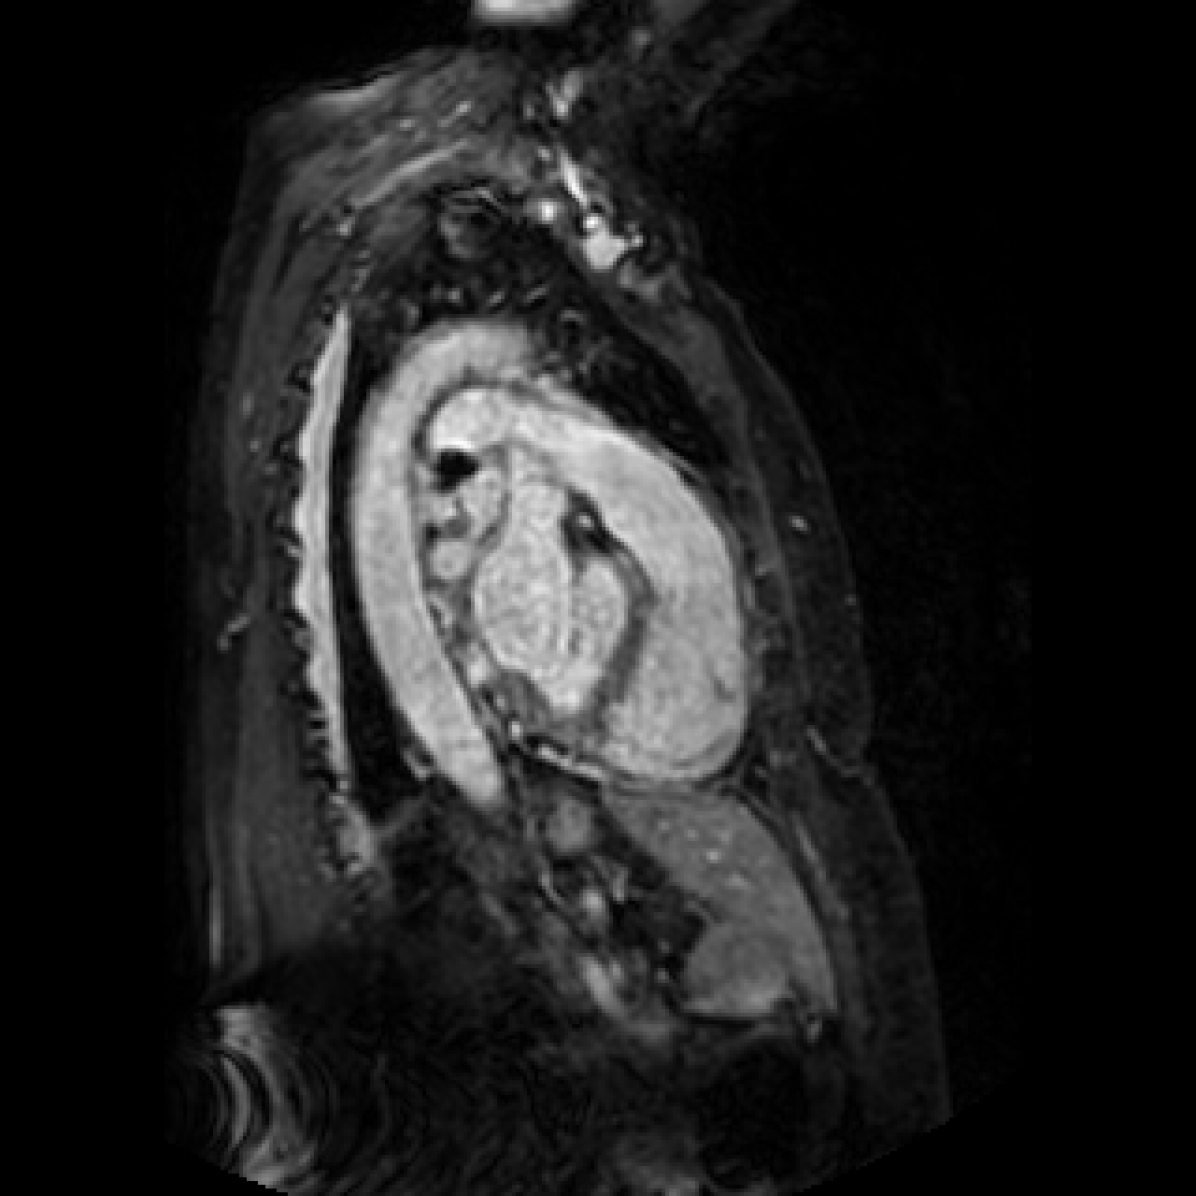

In this section we will show qualitative results of DINOv2 features using principal component analysis (PCA) performed on DINOv2 patch features on X-ray, CT, and MRI scans, following the method delineated in [8]. We will also provide organ segmentation results of linear compared U-Net decoders.

PCA visualization. Figure 2 shows the first three PCA components. The PCA is computed between patches of images that are in the same column, and the first 3 components are shown for X-ray, CT, and MRI scans. Thresholding is used on the first PCA component to remove the background. Just like in natural images [8], the colors of the three PCA components correspond well with the same parts of images in the same category. This is an easier task however, compared to natural images, because there is less variability between examinations on medical images compared to natural images.

U-Net and linear decoder visualization. We also show a visualization of linear and U-Net decoders trained on top of DINOv2 ViT-L/14 features. The linear layer decoder performs surprisingly well, but is limited, especially on smaller masks, due to the smaller decoding map (32x32 pixels interpolated to 448x448) and less adjustable parameters. As expected, the U-Net segmentation results are smoother and represents the ground truth mask more accurately, but is still limited due to the frozen encoder.